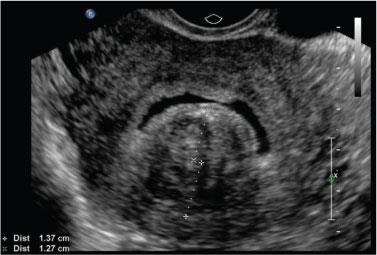

Isthmocele

- When appropriate images have been obtained, deflate the balloon and remove the catheter. If the balloon was in the lower uterus, ensure additional saline images are obtained after balloon removal to fully assess the lower cavity, including a cesarean scar niche, if present

- When appropriate images have been obtained, deflate the balloon and remove the catheter. If the balloon was in the lower uterus, ensure additional saline images are obtained after balloon removal to fully assess the lower cavity, including a cesarean scar niche, if present.

- When appropriate images have been obtained, deflate the balloon and remove the catheter. If the balloon was in the lower uterus, ensure additional saline images are obtained after balloon removal to fully assess the lower cavity, including a cesarean scar niche, if present. This may be difficult if gel remains in the lower uterus.